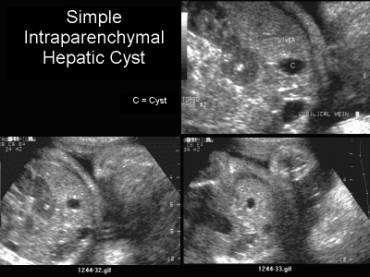

2. Intraparenchymal cysts